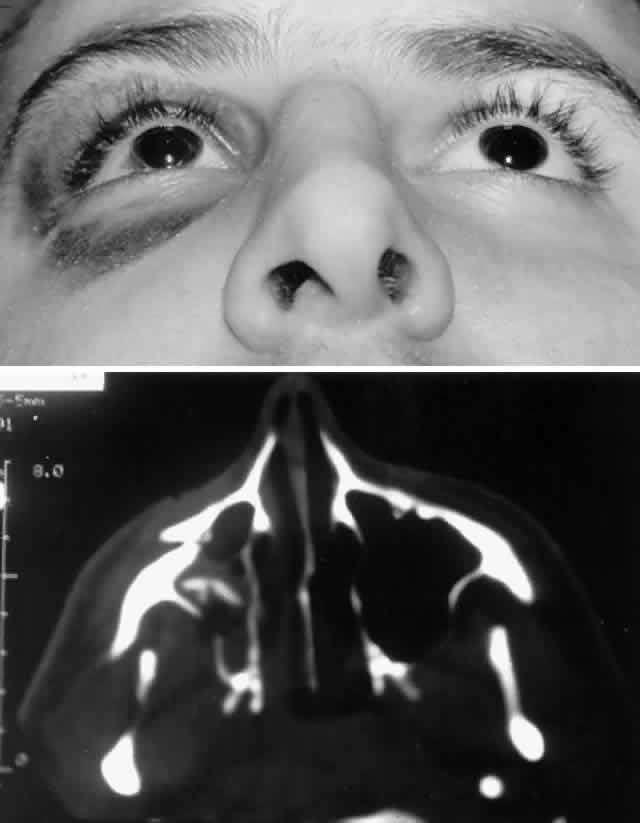

Fig. 8. A. Patient with right zygomatico-orbital fracture. Note flattening of right malar eminence and slight right lateral canthal dystopia. B. Axial CT scan shows displaced right zygomatico-orbital fracture.

LATERAL ORBITAL RIM (ZYGOMATICO-ORBITAL). The lateral orbital rim is composed primary of zygomatic bone. The large zygomatic bone (zygoma) also establishes the malar projection and midfacial width, thus playing a prominent role in facial aesthetics. The zygoma has articulations with the temporal, frontal, maxillary, and sphenoid bones oriented in three different planes. Isolated lateral rim fractures are uncommon, more typically occurring with disruption of the zygoma as a unit.48–54 As previously noted, various names have been used to describe zygomatic bone fracture, including “tripod” and “trimalar” fracture. More recently there has been a trend to refer to such fractures as zygomatico-orbital fractures (or conversely “orbitozygomatic” fractures), which more accurately reflects the prominent orbital component of such fractures.48 Indeed, the main sequelae of zygomatico-orbital fractures are ophthalmic in nature and include enophthalmos, diplopia, infraorbital nerve dysfunction, and lateral canthal dystopia.

In the pathogenesis of a zygomatico-orbital fracture, disruption occurs with various degrees of displacement at each of the articulations of the zygomatic bone. Unlike other portions of the orbit, significant dynamic forces act on the zygoma, primarily due to the masseter and to a lesser extent the temporalis muscle. Significant displacement of the zygomatic segment of the orbit can occur. The zygoma may be rotated inwardly toward the orbit, causing direct damage or functional impairment of the globe, extraocular muscles, or optic nerve. More typically, however, it rotates outward, creating orbital volume expansion and the potential for enophthalmos.

Classification schemes focusing on the different possible anatomic positions (rotations) of the displaced zygoma have been described, but these have not proved particularly helpful for guiding fracture management.51 A classification scheme based on the degree of comminution and displacement is more useful for guiding the intensity of treatment. The classification scheme of Manson and co-workers6 (see the Classification section) is particularly applicable to zygomatic fractures. Low-energy zygomatico-orbital fractures demonstrate little or no displacement. Frequently the fracture is incomplete through at least one articulation with stability provided at this point (typically the zygomaticofrontal suture). Zygomatico-orbital fractures with minimal degrees of displacement do not require reduction. Conservative treatment consists of a soft diet and protection of the malar eminence for several weeks. These patients should nevertheless be followed closely in the initial weeks after injury in order to detect any early zygomatic displacement due to dynamic traction. Zygomatico-orbital fractures with significant displacement are best managed with open reduction and internal fixation (see Figs. 8, 9, and 10). The number of fracture sites requiring fixation varies with the severity of the injury. For middle-energy zygomatico-orbital fractures, which constitute the vast majority of such injuries, mild to moderate displacement is seen, with a range of comminution.